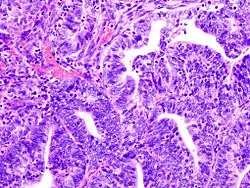

.jpg)

El tratamiento primario es quirúrgico, que consiste en, al menos un muestreo citológico del fluido peritoneal, exploración abdominal, palpación y biopsia de algún nódulo linfático, histerectomía abdominal y remoción de ambos ovarios y trompas de Falopio (denominado salpingooforectomía).[1] La linfadenectomía o el remover los nódulos linfáticos pélvicos y para-aórticos, se realiza a veces para tumores que tiene características de alto riesgo, tales como un tumor patológico seroso o de células claras grado III, la invasión de más de la mitad del miometrio o la extensión hacia la cérvix o anexos. A menudo, puede ser indicado el remover el omento.

Se prefiere la histerectomía abdominal por encima de la vaginal, porque permite al examinador evaluar y obtener lavados de la cavidad abdominal y detectar así mayor evidencia del cáncer.